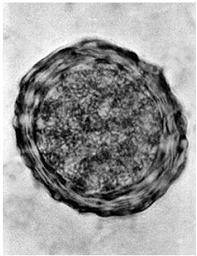

Em um exame parasitológico de fezes, foi realizado o método de sedimentação espontânea e encontrado o ovo ilustrado a seguir. Este ovo pertence a qual parasito?

Ascaris lumbricoides.

Necator americanos.

Trichuris trichiura.

Taenia solium.

Echinococcus granulosus.